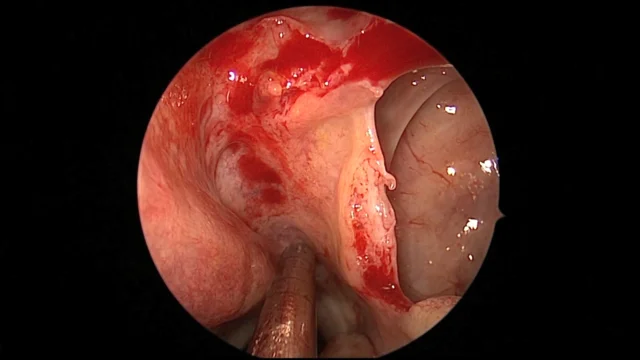

Endoscopic Treatment of Vasomotor Rhinitis